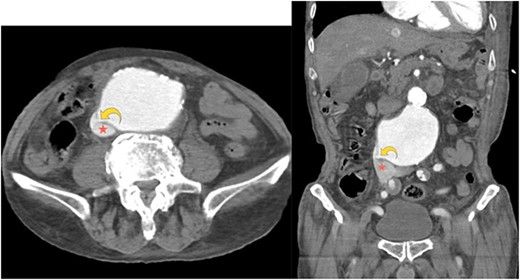

A right-upper quadrant abdominal ultrasound demonstrated an AAA, measuring 5.5 cm × 8.5 cm. Computed tomography angiography of the abdomen and pelvis showed a 9.2 cm aneurysm of the infrarenal abdominal aorta compressing the IVC (Fig. 1a). Furthermore, an aortocaval fistula was noted (Fig. 1a and b). There was no evidence of an aortic rupture or dissection. Of note, the dimensions and anatomy of AAA were amenable to endovascular repair.

Axial computed tomography angiography image showing a small focal defect in the aortic wall (curved yellow arrow). Abnormal early opacification of the IVC (red star) can be noticed in this arterial phase study. These findings are consistent with an aortocaval fistula. No retroperitoneal hematoma is observed.